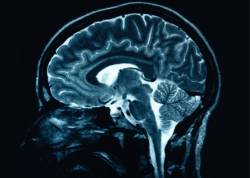

Several studies over the last few years have pointed to a positive association between Alzheimer’s dementia and abnormal glucose metabolism, such as diabetes, elevated blood sugars, and insulin resistance.